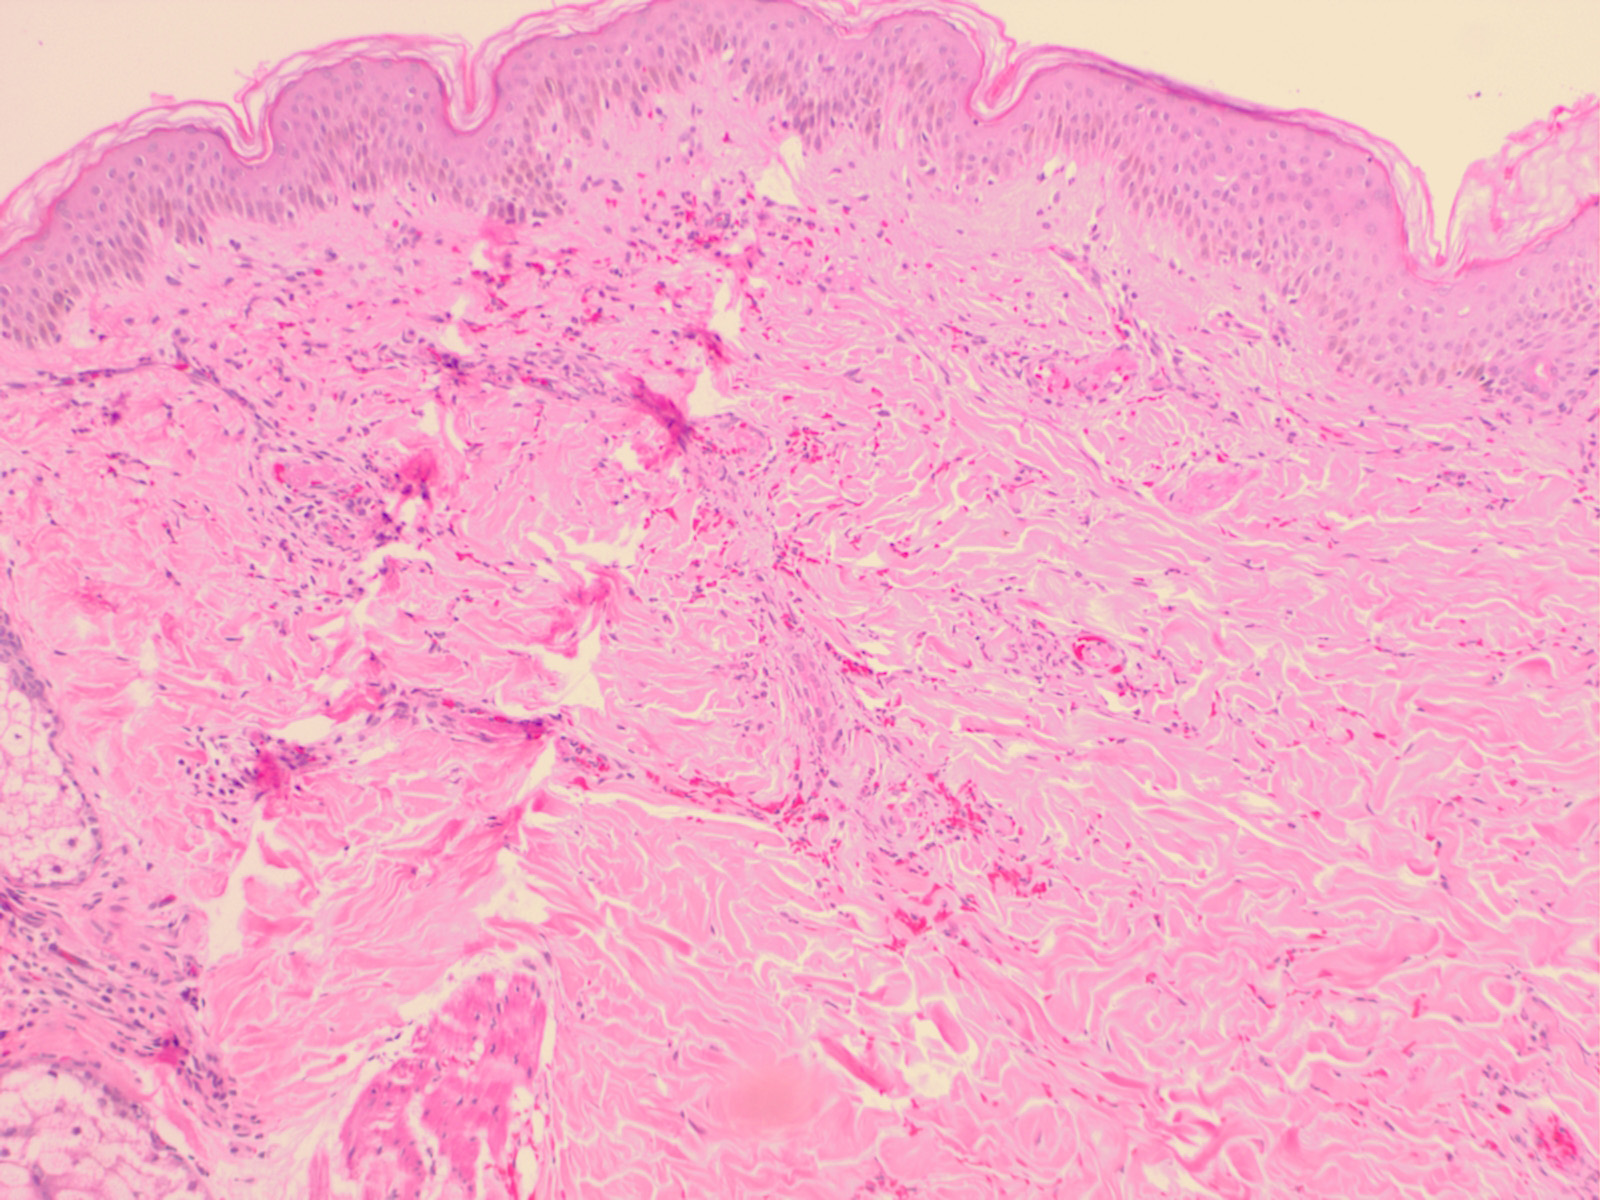

Septic vasculitis = التهاب الاوعية الانتاني